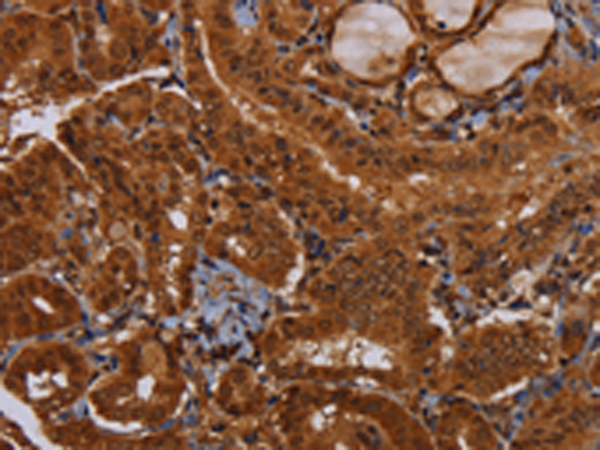

分类: 科研抗体货号: P01531别名: MORG1应用: WB,IHC反应种属: Human, Mouse, Rat

分类: 科研抗体货号: P01583别名: CI-30应用: WB,IHC反应种属: Human, Mouse

分类: 科研抗体货号: P01580别名: B8; CD14; CIB8; MC1DN13应用: WB,IHC反应种属: Human, Mouse

分类: 科研抗体货号: P01606别名: NS; E2IG3; NNP47; C77032应用: WB,IHC反应种属: Human

分类: 科研抗体货号: P01655别名: MPPB; P-52; MPP11; MPPP52; Beta-MPP应用: WB,IHC反应种属: Human, Mouse, Rat

分类: 科研抗体货号: P01604别名: CN1; CNI; CN-I; CN1A; CN-IA应用: IHC反应种属: Human, Mouse